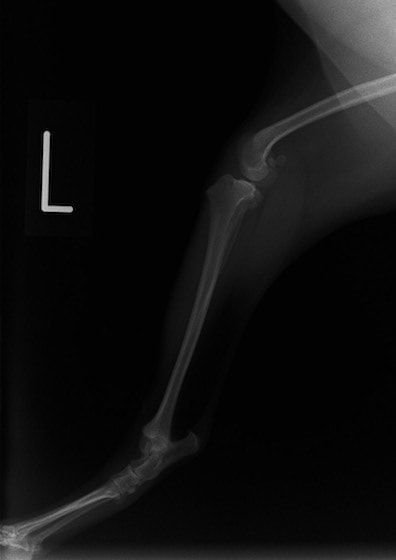

■ 症例22 ポメラニアン 1歳5か月 去勢雄

左後肢の挙上を主訴に来院した。整形学的検査、レントゲン検査より左右の膝蓋骨脱臼(左GradeⅡ〜Ⅲ、右Grade Ⅱ)を認めた。また、脛骨の前方引き出し試験の際に、引き出し兆候は認められないものの、疼痛が認められたため、前十字靭帯の損傷が疑われた。術中における、目視および関節内の操作によって、前十字靭帯の損傷や過伸展といった異常が認められなかったため、膝蓋骨脱臼の整復のみ実施した。手術手技は縫工筋及び内側広筋の解放、脛骨粗面の外側転位、滑車ブロック形造溝術、内外側関節包の縫縮を実施した。本症例は跛行もなく経過良好である。しかし、頸骨高平部の角度(TPA)が 右26.2°、左24.9°であり、解剖学的に前十字靭帯損傷のリスクが高いことから今後の経過に注意が必要である。